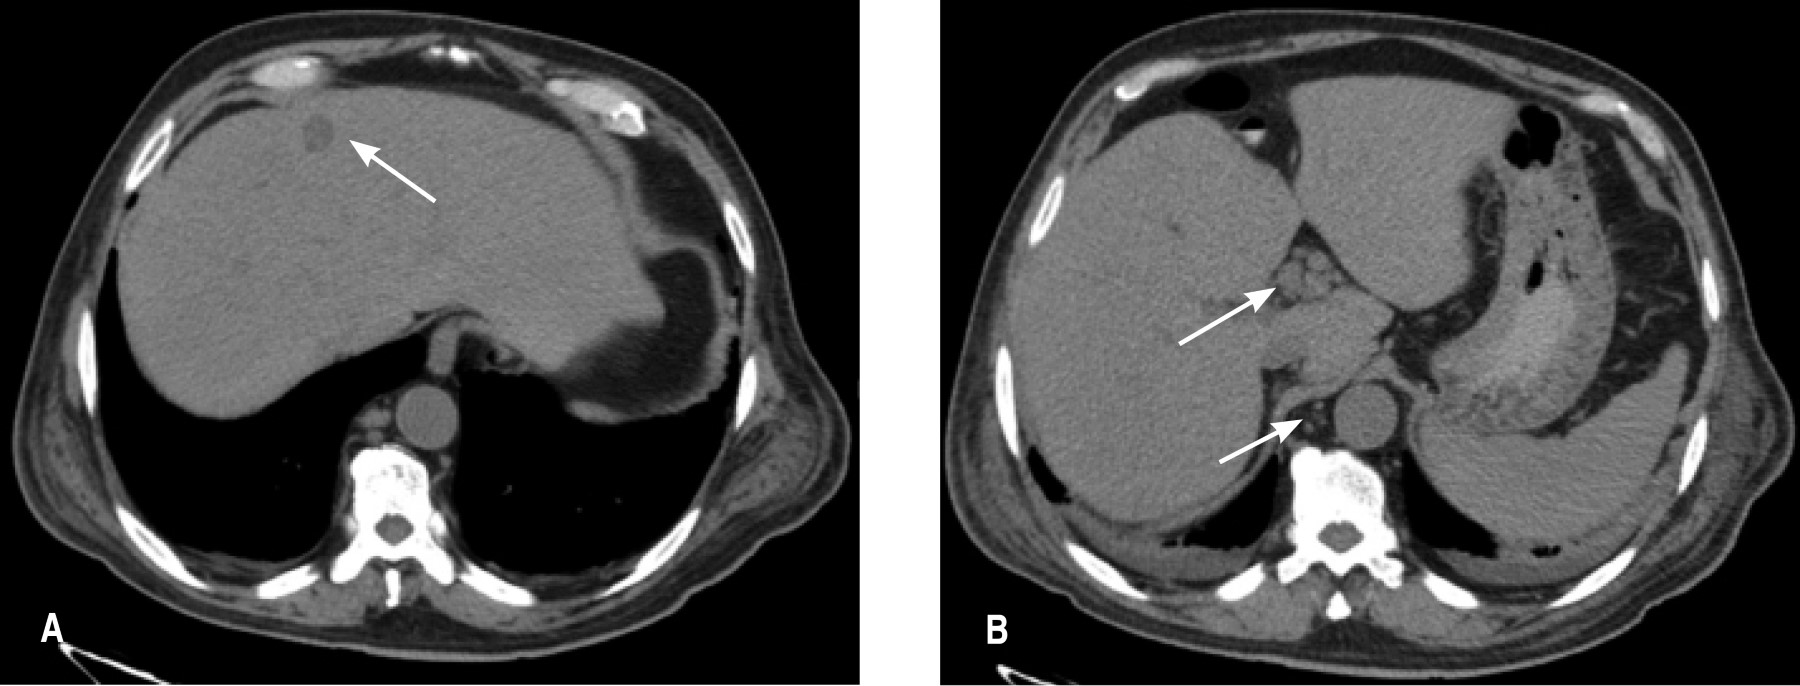

Clínicamente con estabilidad hemodinámica, abdomen distendido, doloroso a la palpación en hipocondrio derecho y fosa ilíaca derecha, se realizaron estudios de laboratorio que reportaron leucocitos 2.8 x 103 μl, neutrófilos totales 87.8%, hemoglobina 6.7 g/dl, hematocrito 20.2%, plaquetas 67 x 103 μl, bilirrubina total 3.04 mg/dl, bilirrubina directa 2.16 mg/dl, bilirrubina indirecta 0.88 mg/dl, panel viral negativo. Se practicó ultrasonografía (USG) de hígado y vías biliares que reportó colecistitis crónica litiásica con datos ecográficos de agudización y hepatomegalia de origen a determinar. La tomografía axial computarizada de abdomen reportó actividad ganglionar a nivel de hilio hepático, peripancreáticos, frénicos, paracólicos y yuxtaintestinales, así como precavos, retrocavos, interaórtico-cavales y paraaórticos, de primario a determinar. Glándula hepática con imágenes de posibles implantes metastásicos localizados en segmentos IV y VI. Vesícula biliar con pared de 6.3 mm, con contenido hipodenso, cambios por colecistitis y escaso líquido perihepático (Figura 2).